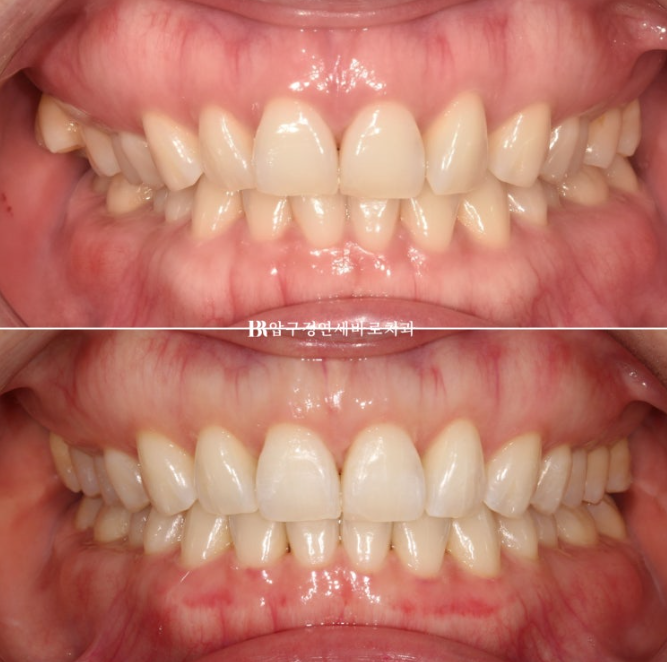

안녕하세요 압구정 교정치과입니다. 23.07~24.05 오늘 포스팅은 인비절라인 라이트 가위교합 벌어짐 소개입니다. 가위교합을 인비절라인 라이트로 해결하고자 오신 환자분입니다. 미니스크류 심고 치료하면 인비절라인 라이트로 가능한 케이스였습니다. 23.07 11개월 간 치료 후 끝났습니다. 중심선 불일치 그리고 오른쪽의...

23.07~24.05

오늘 포스팅은 인비절라인 라이트 가위교합 벌어짐 소개입니다.

가위교합을 인비절라인 라이트로 해결하고자 오신 환자분입니다.

미니스크류 심고 치료하면 인비절라인 라이트로 가능한 케이스였습니다.

23.07

11개월 간 치료 후 끝났습니다.

중심선 불일치 그리고 오른쪽의 맨 뒤 큰 어금니가 바깥으로 나가 있는 가위교합이 정면에서도 잘 보입니다.